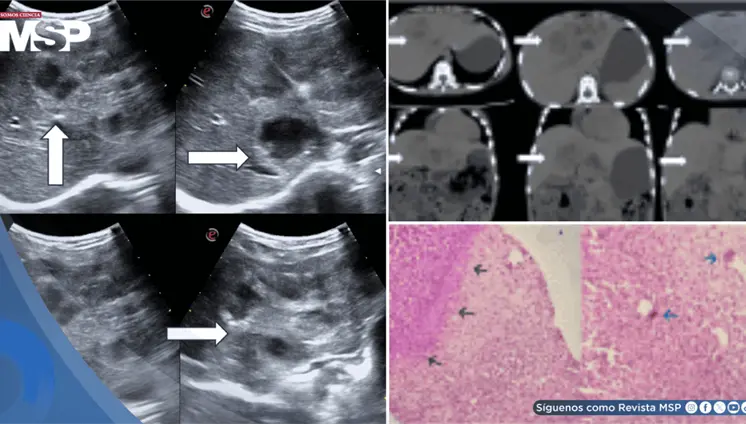

Lo que comenzó como un cuadro frecuente de dolor pélvico y dismenorrea en una mujer, terminó siendo un carcinoma folicular originado en estruma ovárico maligno. La paciente tenía solo 35 años, marcadores tumorales completamente normales y ninguna alteración tiroidea.

La paciente presentó cambios en el hábito intestinal y sangrado rectal con imágenes compatibles con lesiones estenosantes, inicialmente sospechosas de neoplasia sincrónica.

El estudio histológico confirmó un adenocarcinoma mucinoso de células en anillo de sello de vejiga con invasión muscular y diseminación metastásica pulmonar y ósea.